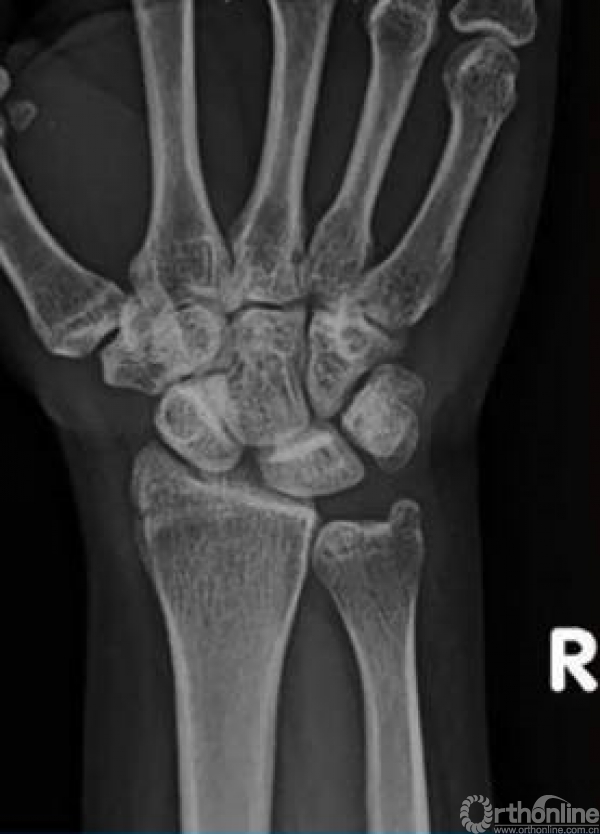

当这些稳定结构都损伤的时候,舟骨出现不稳定。当舟月(SL)韧带出现部分撕裂时,X线可能表现正常,SL韧带完全撕裂的时候舟月关节在应力位下间隙变宽。

复位前。